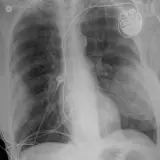

Over 2,100 interactive radiology cases, curated by radiologists for your level of training. Scroll, window, and view cases full screen — just like on PACS. Click linked findings in each writeup to jump straight to them on the image. Cases include sample reports, a focused discussion section, original illustrations, and videos.

PACSで期待されるツールを完備した完全インタラクティブな症例 — スクロール、ウィンドウ調整、ズーム、パン、計測、ROI、フルスクリーンモード。

重要な所見を症例画像上に直接ハイライトする豊富なアノテーション。症例解説内のリンクされた所見をクリックすると、スキャン上の正確な位置へジャンプできます。